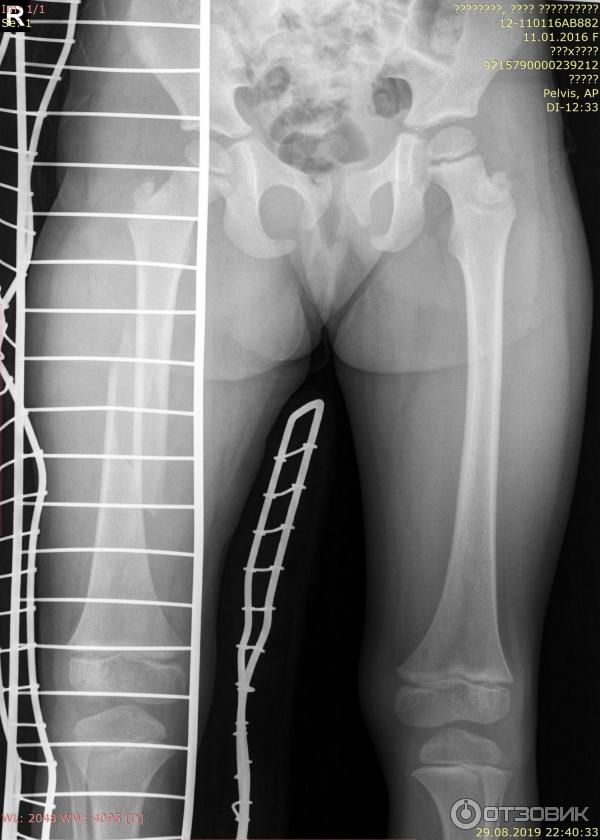

Здоровье на первом месте: диагностика и лечение через рентгеноскопию конечностей

Раздел: Снимки-откровения